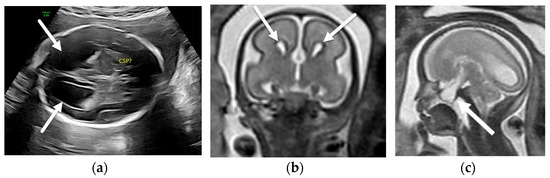

4.1. Holoprosencephaly Spectrum

- Winter, T.C.; Kennedy, A.M.; Woodward, P.J. Holoprosencephaly: A survey of the entity, with embryology and fetal imaging. Radiographics 2015, 35, 275–290. [Google Scholar] [CrossRef]

- Riddle, A.; Nagaraj, U.; Hopkin, R.J.; Kline-Fath, B.; Venkatesan, C. Fetal Magnetic Resonance Imaging (MRI) in Holoprosencephaly and Associations With Clinical Outcome: Implications for Fetal Counseling. J. Child Neurol. 2021, 36, 357–364. [Google Scholar] [CrossRef]